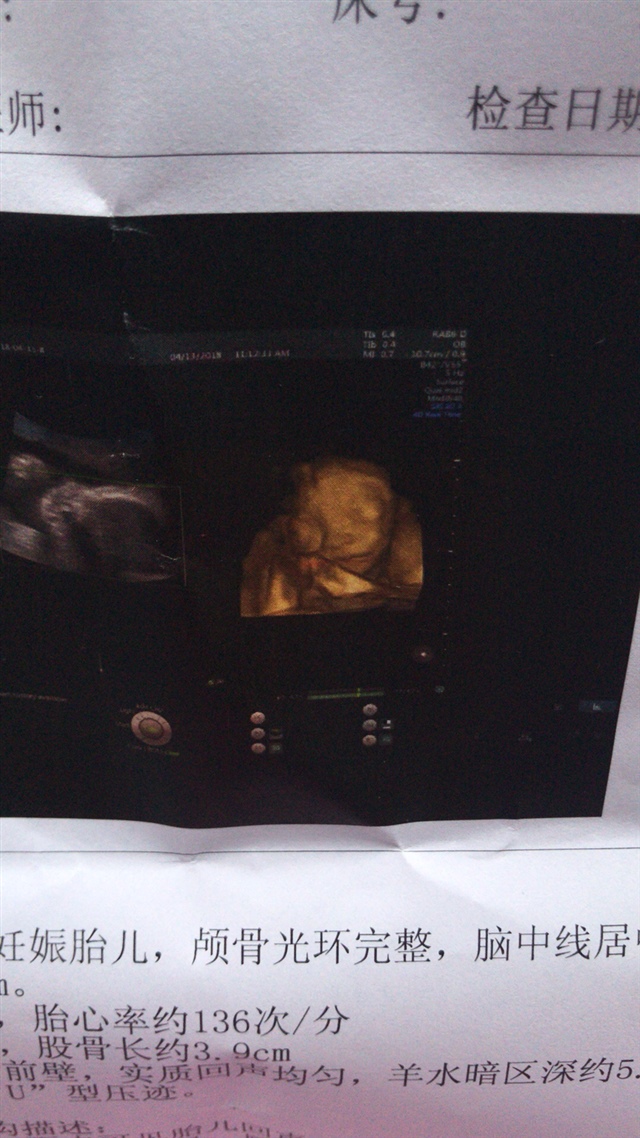

孕16周+0天

诗黛尔微商爆款专卖[帖主]:医生说都正常 我看着别扭